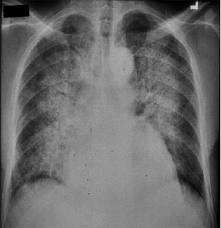

La farmacéutica Almirall ha finalizado con éxito un estudio clínico que confirma la eficacia del bromuro de aclidinio en pacientes japoneses que sufren de Enfermedad Pulmonar Obstructiva Crónica (EPOC).

El ensayo clínico se hizo en pacientes japoneses con EPOC estable, en estado de moderado a grave, que fueron asignados de manera aleatoria en un estudio multicéntrico, doble ciego, paralelo y controlado con placebo.

El aclidinio es un anticolinérgico inhalado de acción prolongada, aprobado por las autoridades sanitarias en Europa y EEUU como tratamiento de mantenimiento a largo plazo del broncoespasmo asociado a la enfermedad pulmonar obstructiva crónica, incluyendo bronquitis crónica y ensifema. (EFE)